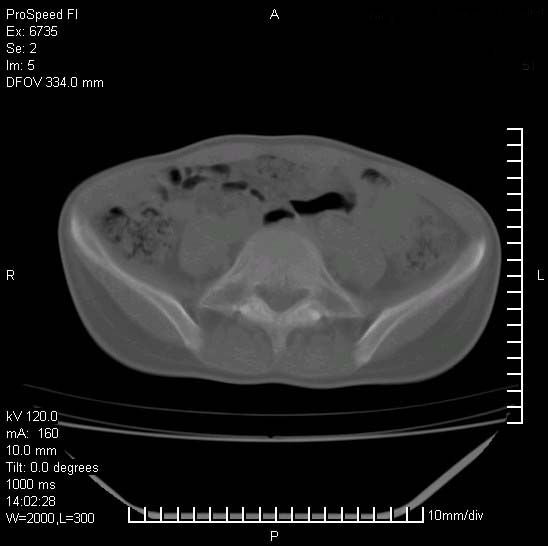

患者自诉胯部疼痛两年余,在当地服用中药,半月前至本院考虑骶髂关节结核,给予抗痨治疗。现发展至右下肢疼痛明显,活动受限,以膝关节处明显,拍膝关节平片无明显异常。

两侧骶骼关节改变,考虑强直性脊炎

左侧骶髂关节面限局性骨破坏,边缘硬化关节腔见钙化物;不出外tb

右侧骶髂关节也有类似改变,只是较左侧轻,首先考虑强直性脊柱炎,不除外结核,建议作hla-b27检查。

典型强脊炎改变,髋关节亦有累及

符合强直性脊柱炎表现。